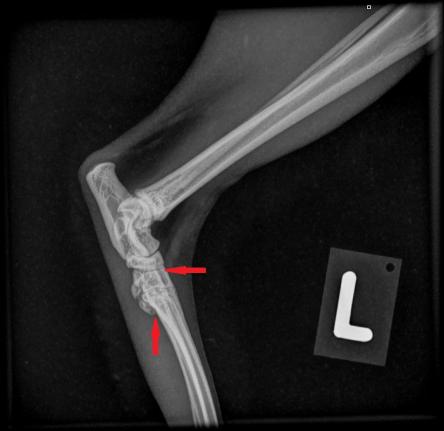

Die Besitzerin berichtet, dass der Kater recht lahmheitsfrei laufe, aber nicht über eine grosse Sprungkraft verfüge. Die Beine von Maxwell sind eher kurz und er scheint hinten und vorne X-beinig. Der Gang der Katze wirkt staksig; eine eigentliche Lahmheit ist nicht zu sehen. Um Aufschluss über die Situation in den Gelenken zu erhalten, werden die Vorderpfoten/Handgelenke, Hinterpfoten/Fusswurzelgelenke und die Wirbelsäule geröntgt. Es ist zu erkennen, dass Hand- und Fusswurzelgelenke gegenüber der Normalsituation eine X-beinigkeit (Valgisierung) aufweisen, an verschiedenen Stellen Anzeichen einer Arthrose vorhanden sind und insbesondere die Mittelhand- und Mittelfussknochen kurz und gedrungen erscheinen. Ein Teil der Fusswurzelknochen von Maxwell sind ausserdem zu einem einzigen Knochen verwachsen.